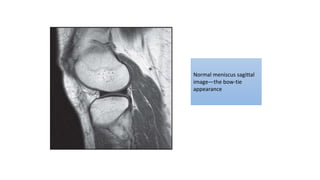

Normal meniscus sagittal

image—the bow-tie

appearance